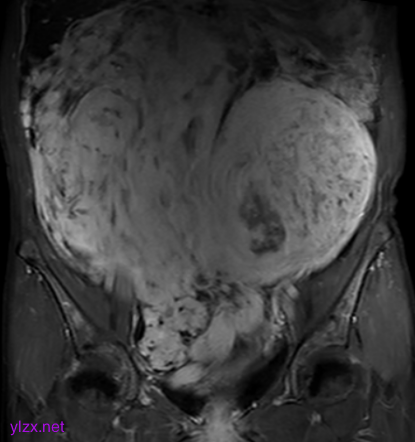

MRI检查:

子宫右侧巨大实性占位,大小约260×110×91mm,与子宫分界不清,T1WI呈稍低信号,T2WI呈不均匀稍高信号,呈束状、旋涡状改变(图1),病变内部分可见囊变,肿瘤内部及表面多发流空血管影(图2);DWI上病变呈略高信号,ADC图呈略低信号,ADC值为1.633×10-3 mm2 /s;增强扫描呈明显强化(图3),内部见条片状低信号。影像学考虑子宫右侧恶性肿瘤。

图3

子宫PEComa影像学表现各异,其MRI表现具有一定的特征,肿瘤T2WI信号稍高,呈束状排列,富血供,可伴有变性、坏死,肿瘤内部及表面可见多发流空血管影。